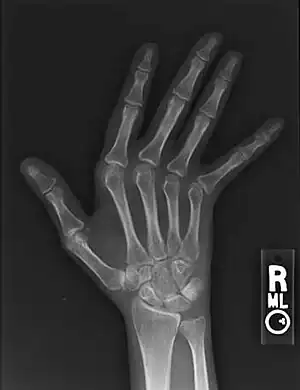

| Jaccoud arthropathy seen on a hand x-ray. As opposed to arthropathy due to rheumatoid arthritis, there are no erosions. | |

Jaccoud arthropathy (JA), is a chronic non-erosive reversible joint disorder that may occur after repeated bouts of arthritis.[1][2] It is caused by inflammation of the joint capsule and subsequent fibrotic retraction, causing ulnar deviation of the fingers, through metacarpophalangeal joint (MCP) subluxation,[1][3] primarily of the ring and little-finger.[3] Joints in the feet, knees and shoulders may also get affected.[1] It is commonly associated with systemic lupus erythematosus (SLE), and occurs in roughly 5% of all cases.[1][2]

Plain hand radiographs typically show marked ulnar subluxation and deviation at the metacarpophalangeal joints. Absence of erosions is a notable feature, although occasionally "hook" erosions may be observed, which are similar to those seen in SLE and ankylosing spondylitis. Evidence of muscle (soft tissue) atrophy also may be present.